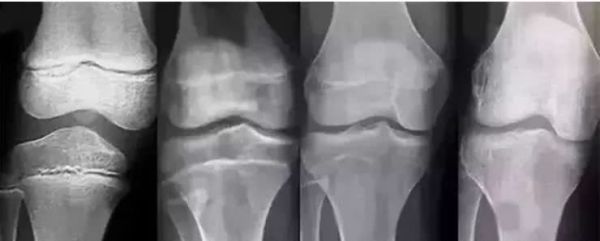

小张两口子,一个1.85米,一个1.68米,可是小小张今年13岁了,但看起来比同龄的孩子却差一大截,甚至有比小小张年龄小很多的孩子都比小小张高出很多。按道理不应该呀,父母都是挺高的,小小张怎么会不长高呢?是什么原因呢?最后小张夫妇下定决心,决定还是带孩子去医院看看,到底是不是晚发育。结果发现小小张骨骺愈合只剩一条缝了,根据其闭合程度来预测小小张长高空间已经不大了,原来是小小张青春期开始较早,最终身高矮小。

到底是什么原因导致小小张早熟呢?原来小张夫妇平时比较忙,小小张要买吃的,就总是给钱让小小张自己去买,孩子怎么能抵挡花花绿绿的包装,麻辣鲜香的垃圾食品的诱惑?钱就全买垃圾食品了,总是垃圾食品,那就很容易影响到孩子的身高发育。幸运的是小小张骨骺线还没有完全闭合,还有希望,最后医生根据小小张闭合程度来预测长高空间,制定科学的身高管理方案,有计划的增高身体,这个结果就不用多说了。